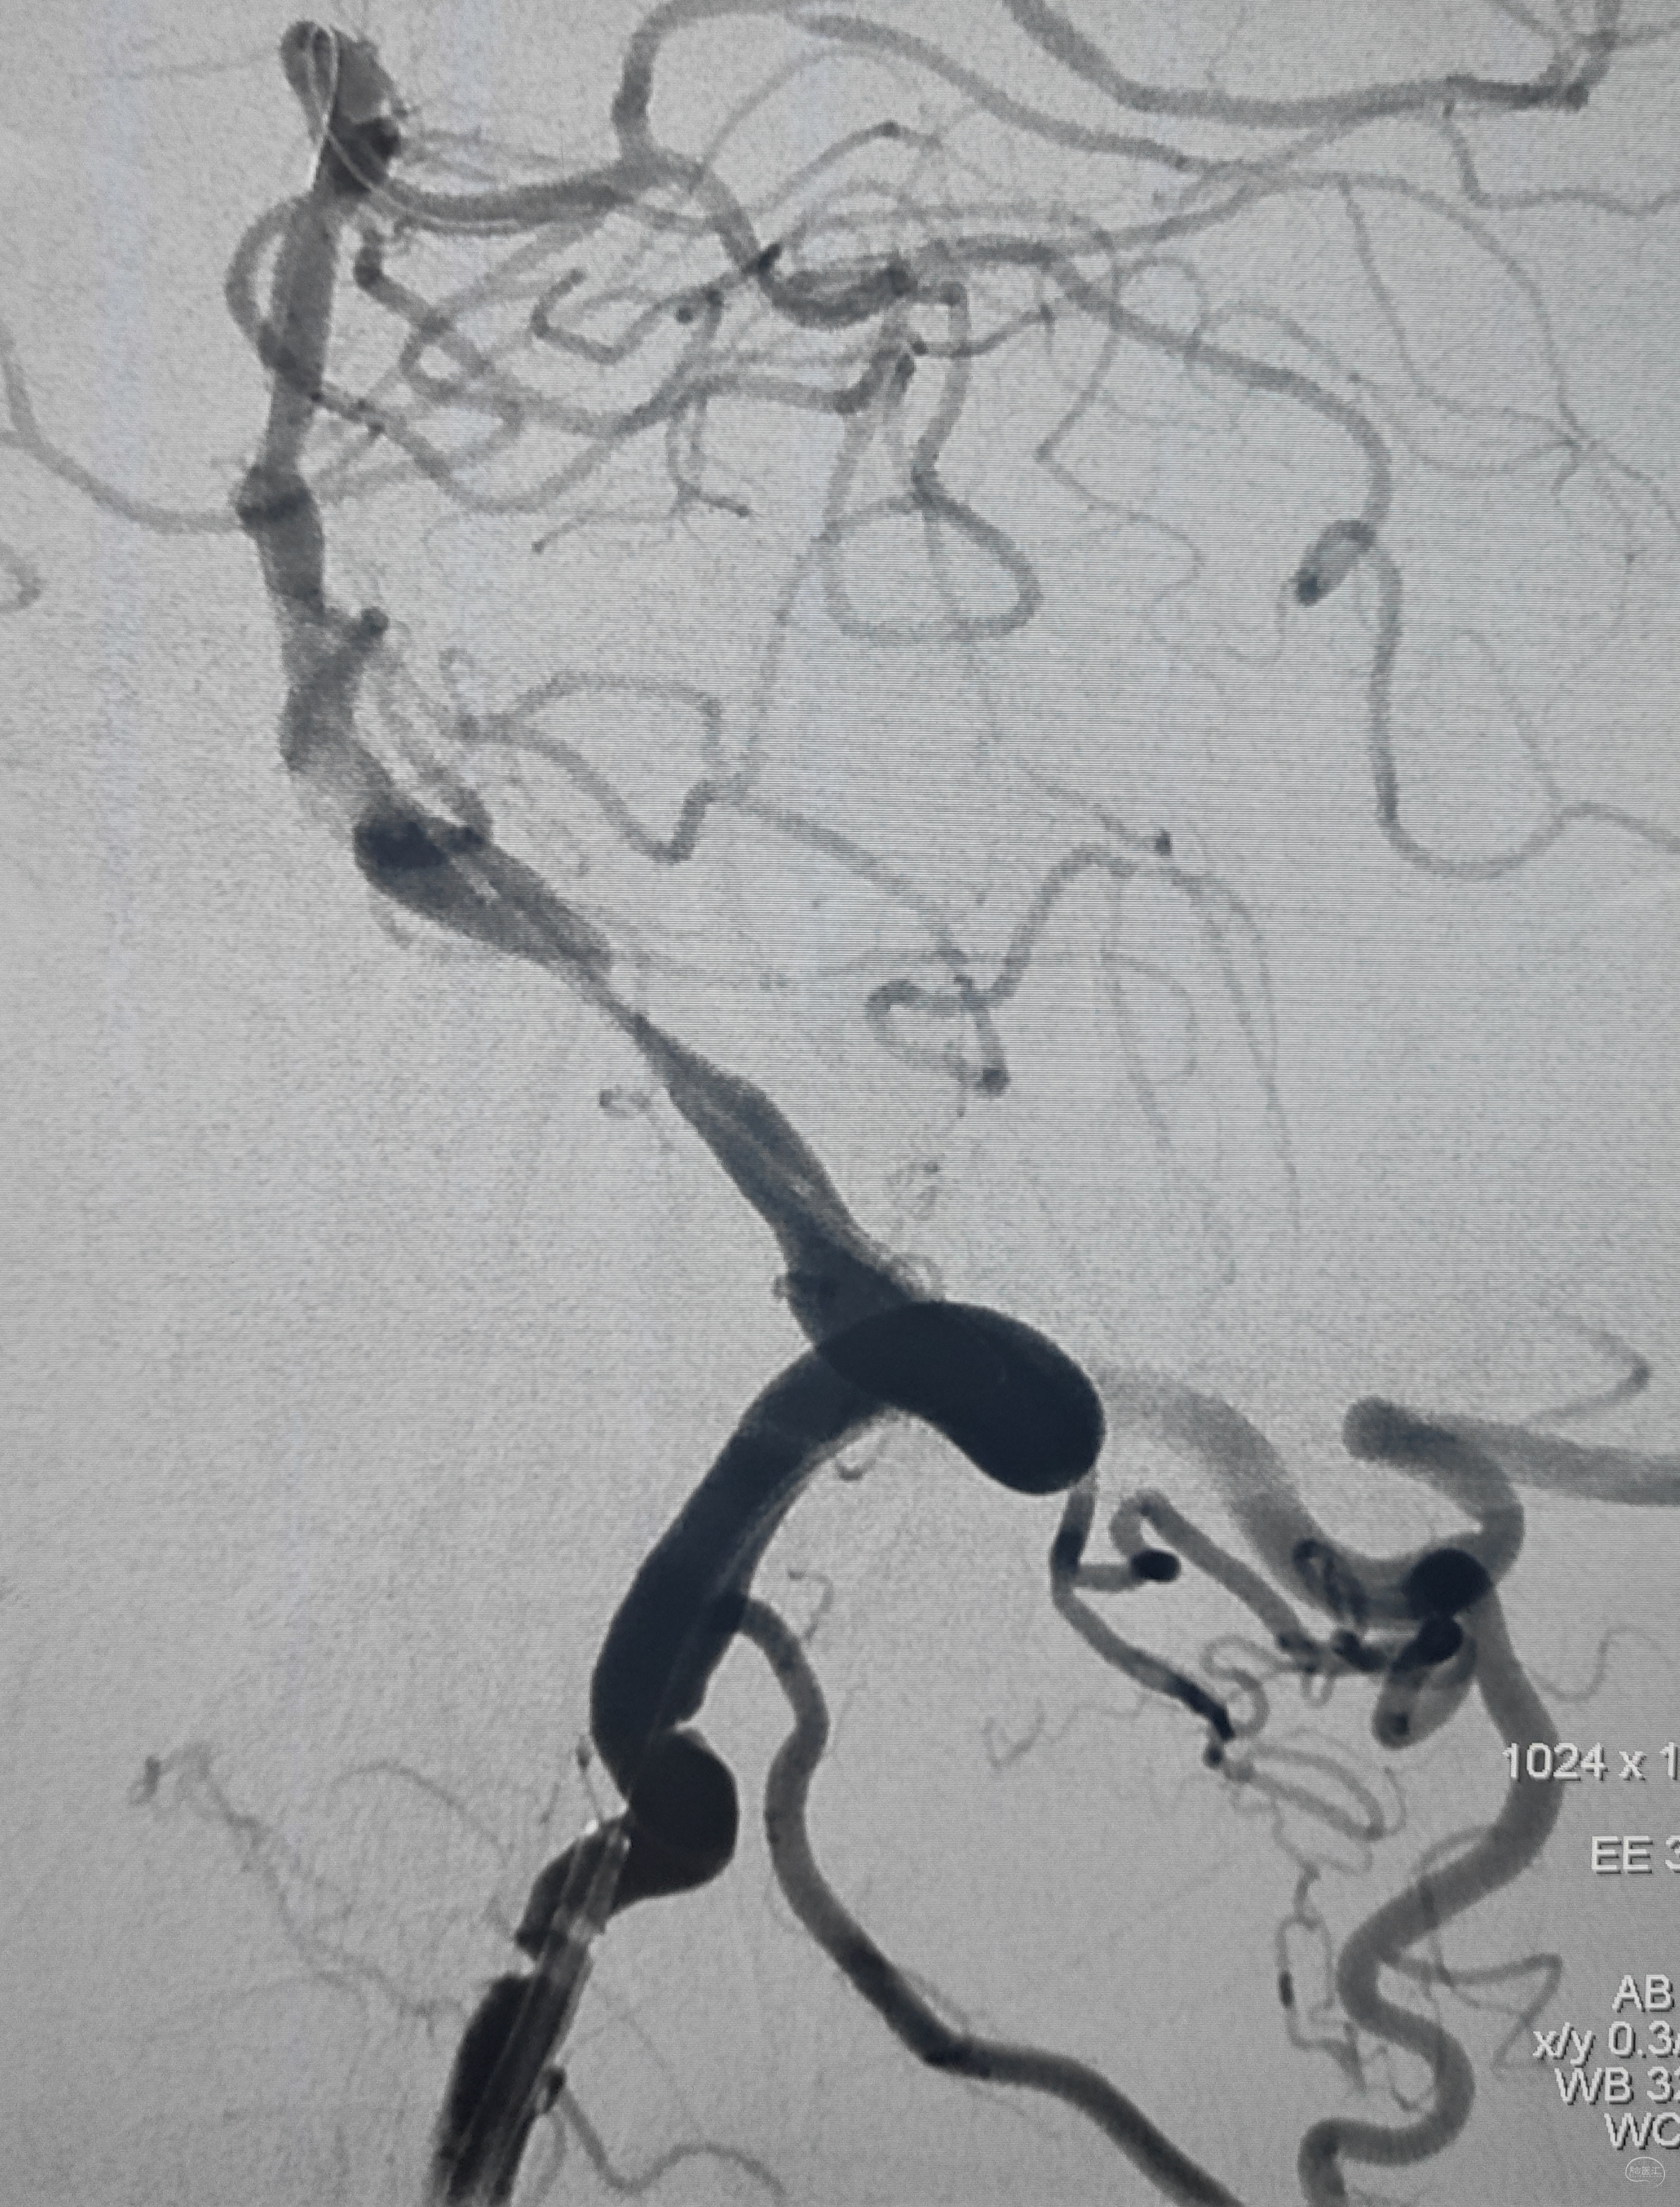

右侧颈总动脉正侧位造影:意料之外的是,枕动脉通过肌支与右侧椎动脉吻合(紫色箭头),像极了《大风吹》的歌词“借一杯天上的水”,源源不断进行着血流的补充。但是好景不长,同侧V4段明显狭窄,无情的设置了第二道坎(绿色箭头)。

左侧颈总动脉造影:颅内床突段以远基本闭塞,仅残涓涓细流,血供极差,脑膜中动脉瘤仅少量代偿,确实不容易,这估计就是想来搭桥的初衷了吧。

术后即刻造影,右侧椎动脉显影佳,并向左侧前循环代偿供血良好